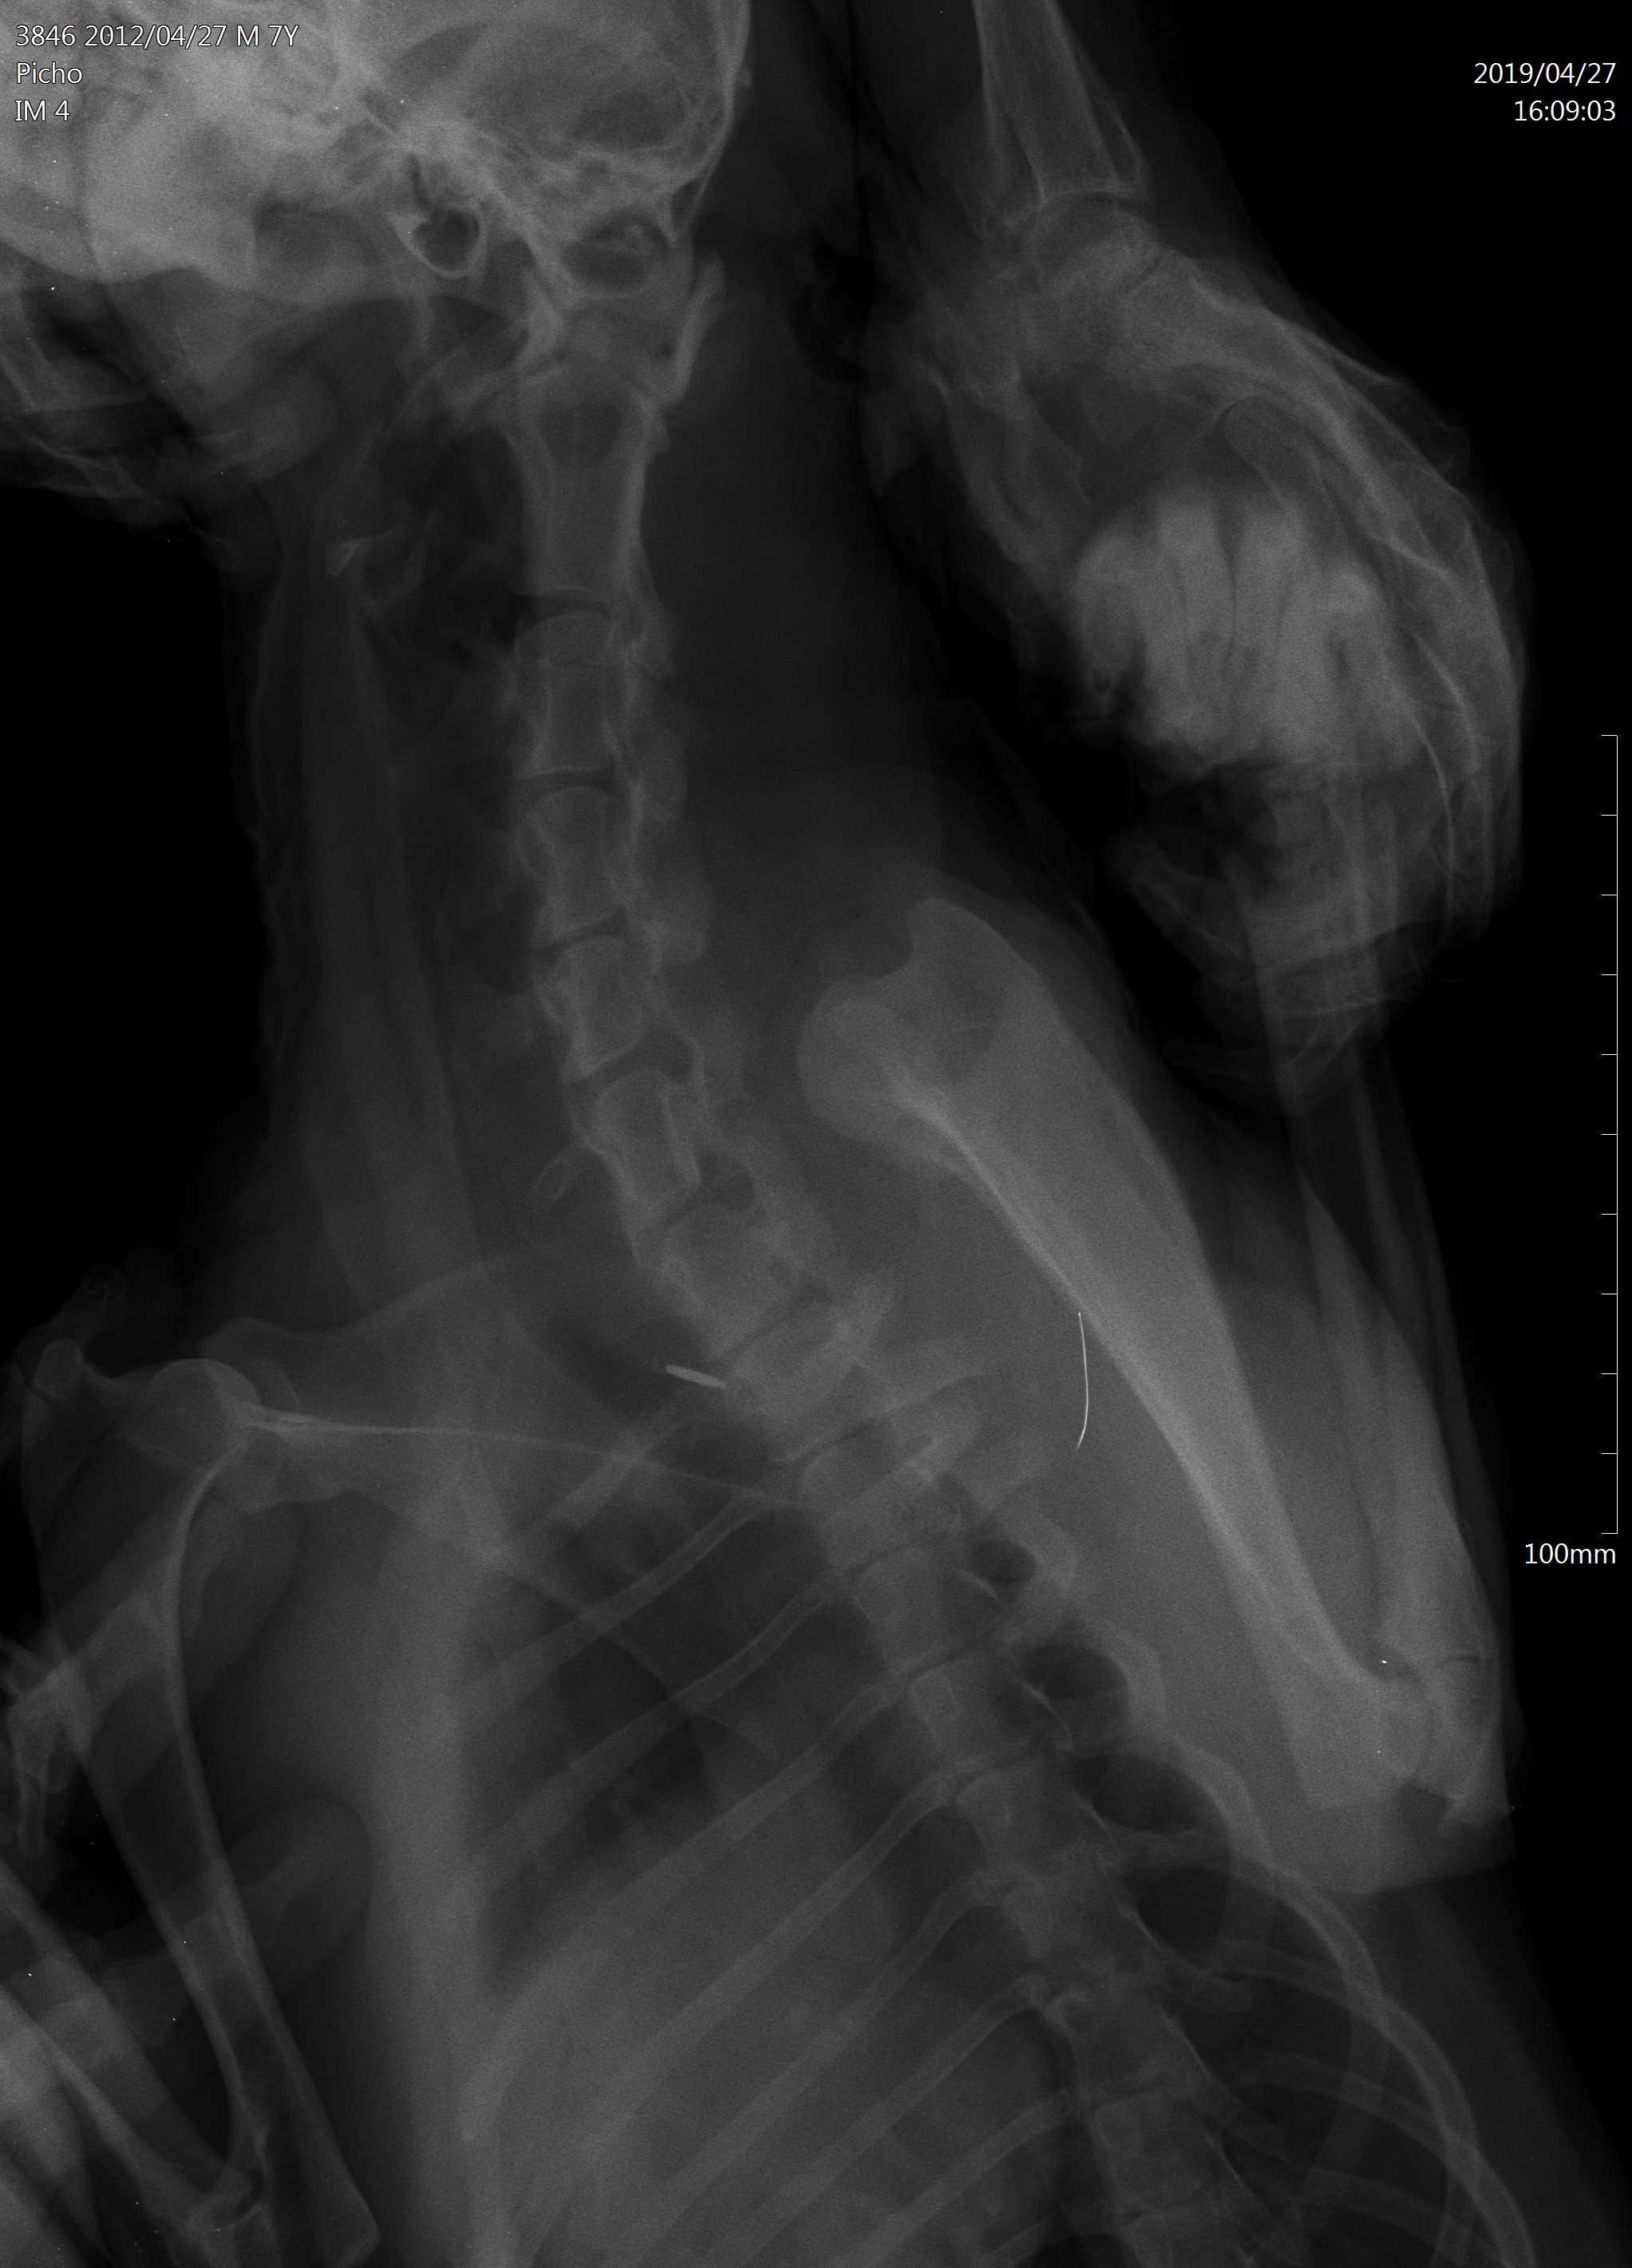

Dears, My dog had a seizure 1 month ago, 2 days ago he was vomiting. Then he was playing with my daughter and she accidentally hit him somewhere in the neck as she says, in the morning we found him paralyzed with all legs he can't walk. We had an X-ray, attached see pics. Our Vet said it could be a tumor he did a surgery, our dog dies 2 days after with tromboembolia sadly. Please advise according to Xray my vet was right or not? Could my daughter caused the tumor?